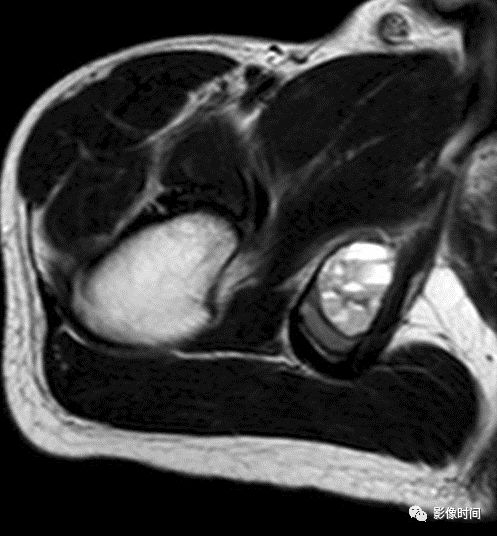

四、肿瘤内液-液平面

肿瘤内液-液平面多数是病灶内囊变出血所致,MRI T2W1 为上部呈高信号下部呈中低信号的液-液平面。CT 可为上部低密度下部高密度的液-液平面(图 32)。液-液平面常见于动脉瘤样骨囊肿、但也可见于骨内腱鞘囊肿(图 33)、囊性血管瘤病等其他肿瘤和肿瘤样病变。

图 32 肿瘤内液-液平面:动脉瘤样骨囊肿

图 33  肿瘤内液-液平面:动脉瘤样骨囊肿

图 34  肿瘤内液-液平面:骨内腱鞘囊肿